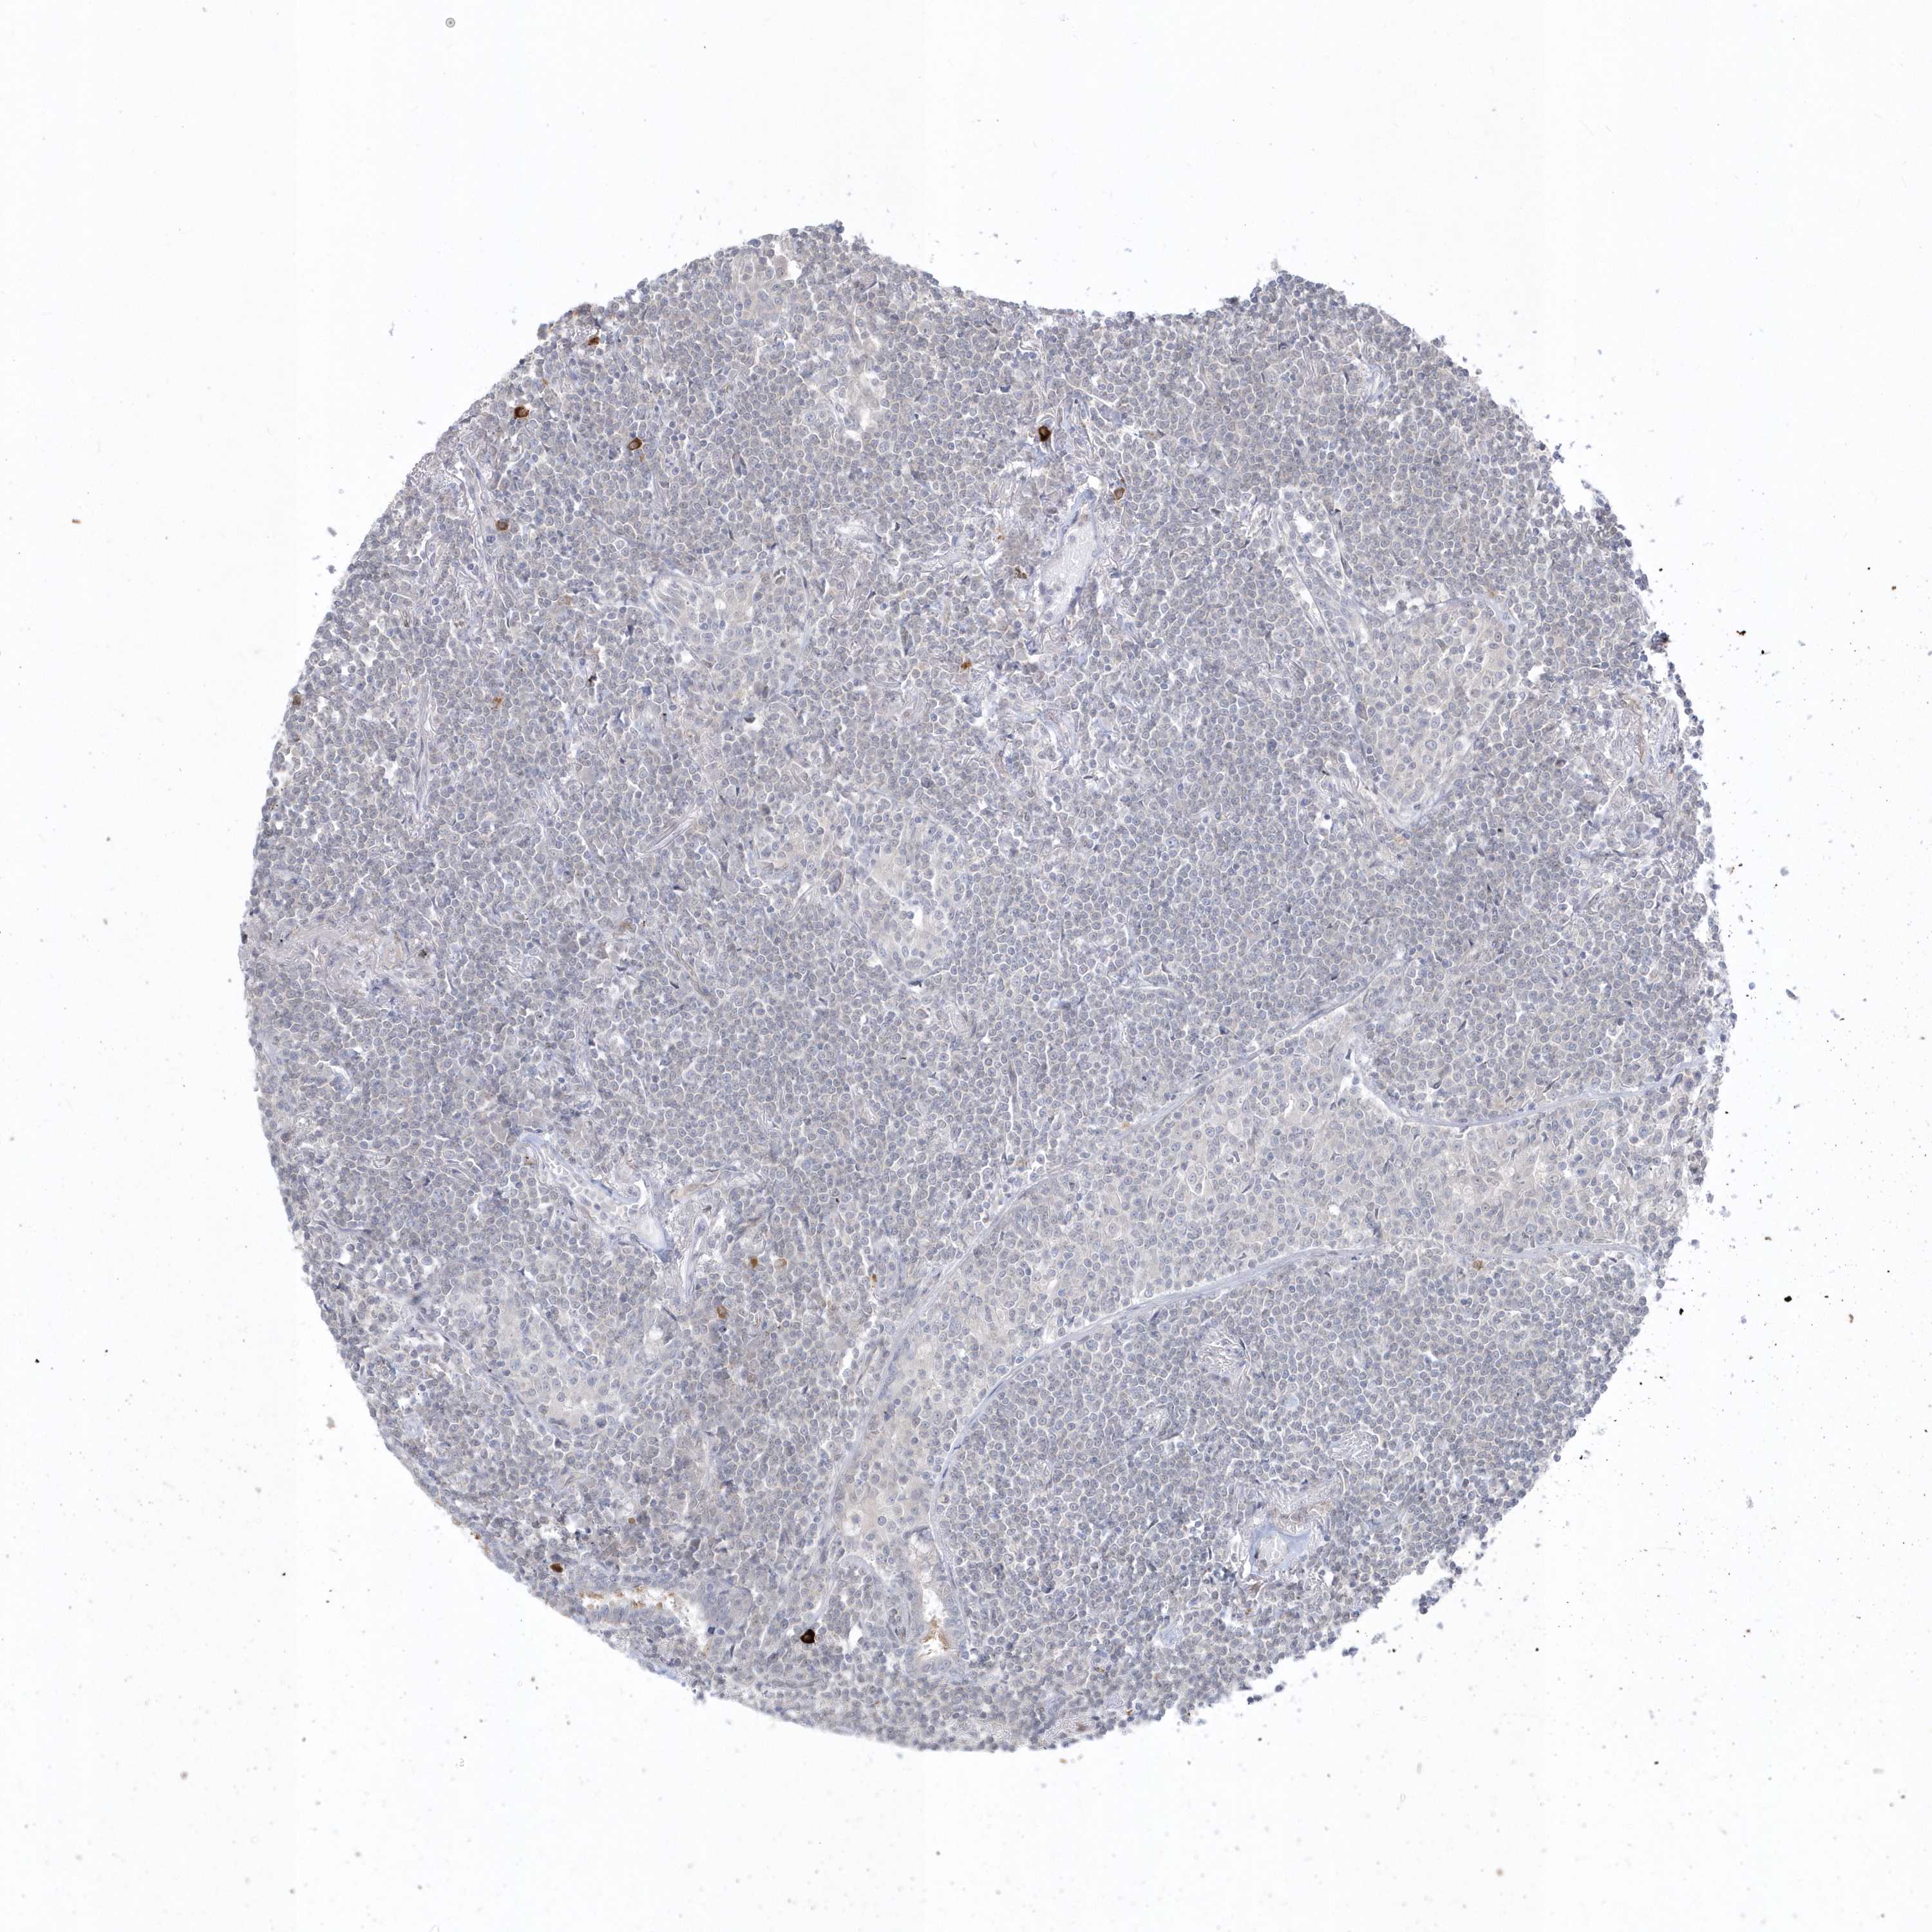

CANCER LYMPHOMA Show tissue menu

LYMPHOMA - Protein expressioni

A mouse-over function shows sample information and annotation data. Click on an image to view it in a full screen mode. Samples can be filtered based on level of antibody staining by selecting one or several of the following categories: high, medium, low and not detected. The assay and annotation is described here.

Each image is clickable and will lead to virtual microscopy that enables deeper exploration of all samples and also displays staining intensity scores, fraction scores and subcellular localization as well as patient and tissue information for each sample.

Antibody HPA036160

Staining

High

Medium

Low

Not detected

Intensity

Strong

Moderate

Weak

Negative

Quantity

>75%

75%-25%

<25%

None

Location

Nuclear

Cytoplasmic/membranous

Cytoplasmic/membranous,nuclear

Hodgkin's disease, NOS

Malignant lymphoma, non-Hodgkin's type, High grade

Malignant lymphoma, non-Hodgkin's type, Low grade